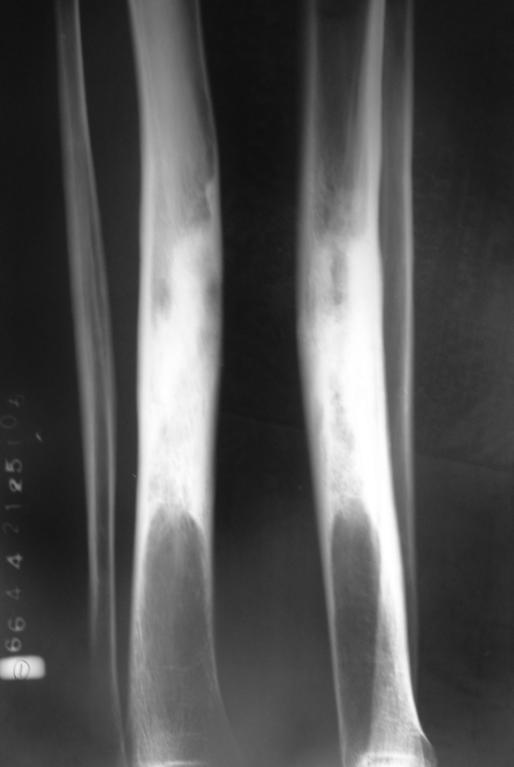

临床:1、年龄:青少年(11-20岁占50%),男多于女;2、部位:以膝关节、肱骨上端多见。;;发生于干骺端。

影像学表现:1.源于骨髓腔的不规则的骨破坏和骨增生;2.骨皮质破坏,骨膜增生–葱皮样、放射状,Codman三角(袖口征)-骨膜增生被破坏形成

3.软组织肿块,其内见肿瘤骨(诊断骨肉瘤要点)。云絮状、针状、放射状、斑块状

桡骨上段成骨型骨肉瘤:骨质增生硬化,并有骨膜反应,软组织肿块

股骨下端溶骨型骨肉瘤